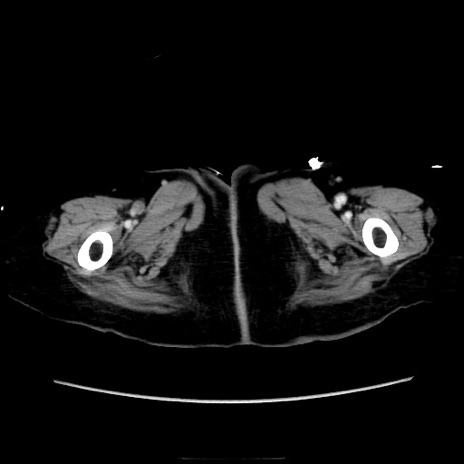

症例40(横断像)

横断像